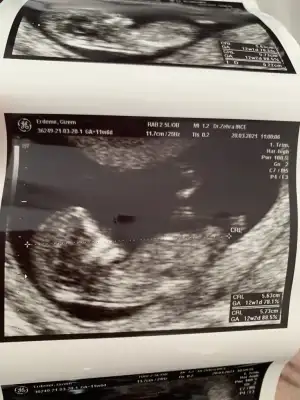

Kızlar merhaba 12 hafta cinsiyet tahmini yapabilcek olan var mı 😁

Eklentiler

• 5E368925-A43A-4A8F-AEE6-5113FA2431A6.webp

5E368925-A43A-4A8F-AEE6-5113FA2431A6.webp

43,8 KB · Görüntüleme: 68